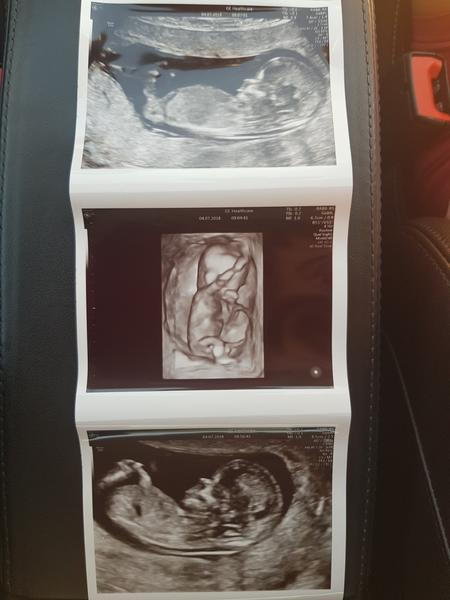

@tercasv ony ty cizí fotky na internetu jsou něco jiného, než když pak člověk vidí toho svého cvrčka 🙂 Mě tedy zase tak moc neoslovily přímo ty fotky - byť se nám povedly docela hezky, ale líbil se mi ten zážitek. Je vidět, jak se tam miminko tváří, jak zívá, dělá ksichtíky........🙂

Za mě fajn cesta do hlubin ...maminčina bříška - moc me bavilo, když jsem pak našla fotku ze 3D a fotku reálnou, které byly témeř totožné - tvář, výraz......

Musím říct, že to bylo super. Přesto, že nejsem zrovna hubená a mám placentu na přední straně, tak bylo mimčo krásně vidět. Oproti těm skoro mazaninám od gynekologa nesrovnatelné....

@tercasv Ja od toho moc neocekavala, premluvil me manzel, ze to zkusime, ze bychom treba litovali. Malej se nechtel ukazat oblicejem, takze jsme si dobre prohledli jeho zadek a naprosto presne vedeli, ze to bude kluk🙈 Pak se ale ukazal a stalo to za to. Mam fotku, kterou mam stale vytavenou na stole a rada se koukam, jak si byl po narozeni podobny, vcetne jeho mimiky😀 U me to tedy predcilo ocekavani, nejen ten vysledek, ale i ten zazitek byl fajn😀.

Stojí - ale až tak v tom cca 23-28 týdnu 🙂 to už je krásně vidět obličejík. Já mám od dcery i syna i moc pěkná videa 🙂